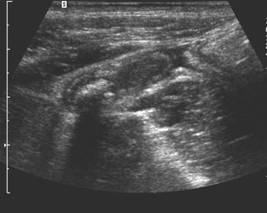

PARTE SPECIALA LITIAZA BILIARA

PARTE SPECIALA LITIAZA BILIARA - MOTIVATIA LUCRARII - Litiaza biliara este cea mai frecventa afectiune a vezicii biliare, ea afecteaza un procent important al populatiei: 10-20% din indivCiteste tot ... 13404 cuvinte

Dimensiune mare

+ cu imagini |

Explorari paraclinice - apendicita

Explorari paraclinice - apendicita 1 Analize de laborator Leucocitoza moderata, intre 10.000 18.000 / mmc , este de obicei prezenta la pacientii cu apendicite acute, necomplicate si deseorCiteste tot ... 477 cuvinte

Dimensiune mica

+ cu imagini |